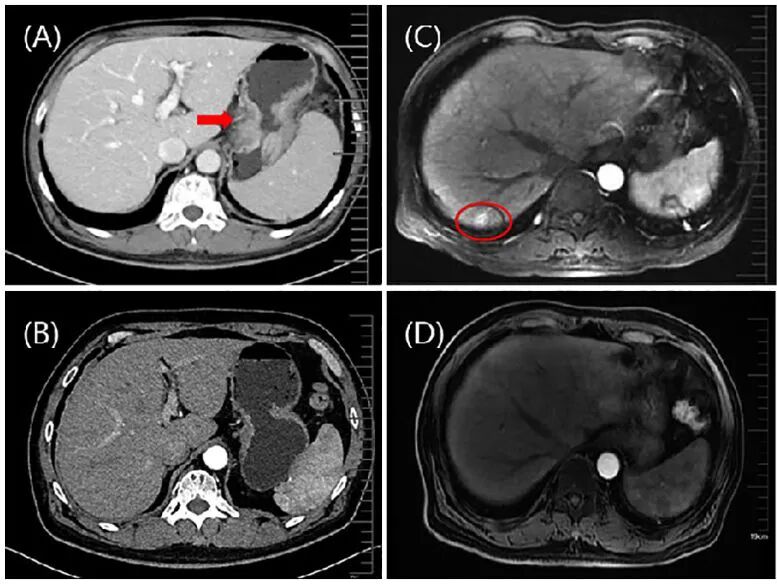

2020年9月底行体格检查,显示双侧锁骨充盈,右侧锁骨上区域淋巴结坚硬且固定,大小约2 ×2厘米,无压痛。 2020年9月28日行腹部和盆腔CT,显示胃底和体壁明显、不均匀增厚(下图A)。考虑脾脏、胰体/胰尾或脾静脉侵犯可能。病灶周围以及腹膜后和纵隔区域的多个淋巴结肿大,MIR提示多发性肝转移(下图C)。

8周后,CT与MRI评估显示肿瘤部分缓解(下图B、D)。